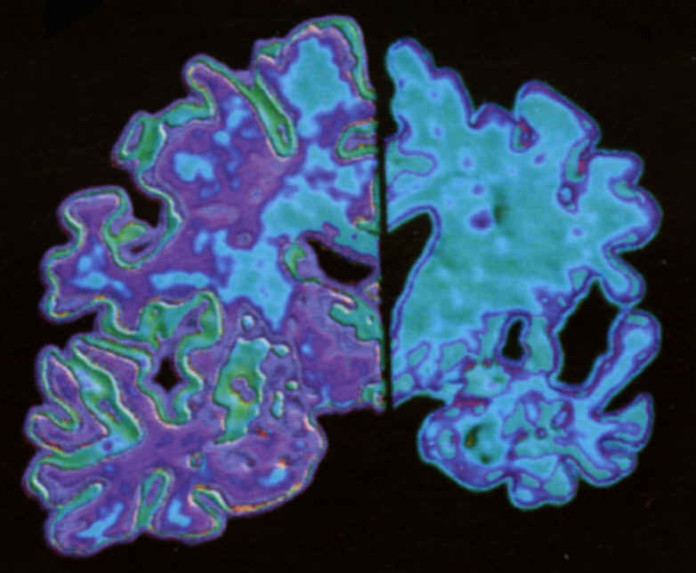

Enfermedad de Alzheimer es una enfermedad neurodegenerativa progresiva asociada con la producción y acumulación de péptidos beta-amiloides producidas por APP disociando los bits. Mientras que varias formas mutantes del gen APP se han relacionado con inicio temprano, las formas agresivas de la EA, hay una evidencia que apoya un papel limitado para las mutaciones en el gen de la más común forma de inicio tardío de la enfermedad.

La enfermedad de Alzheimer disease, neurodegenerativa Progresiva UNA disease, es la forma Común mal de demencia que afecta a Ocho al Ciento Cuatro de Población del mundo-la de Ancianos. Las características neuropatológicas de su hijo y su presencia de placas amiloides extracelulares y ovillos neurofibrilares intracelulares del hipocampo en El y la del cerebro la materia gris cortical del Alzheimer.